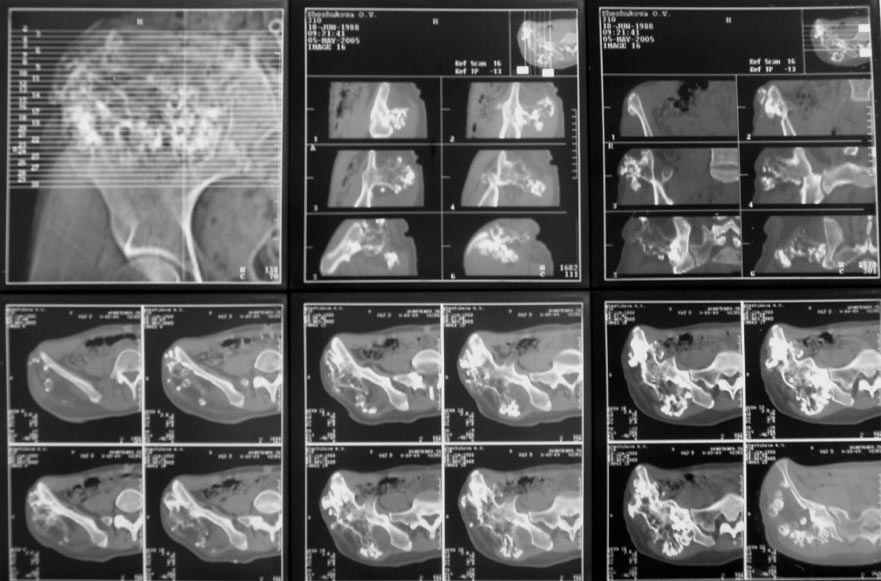

Уважаемые коллеги! К нам поступила пациентка 16 лет с диагнозом: остеохондрома крыла правой подвздошной кости.

Учитывая большие размеры образования, необходимо удаление его с резекцией крыла подздошной кости вместе с ее гребнем. Предполагается наличие большого дефекта. Поделитесь опытом закрытия таких дефектов.